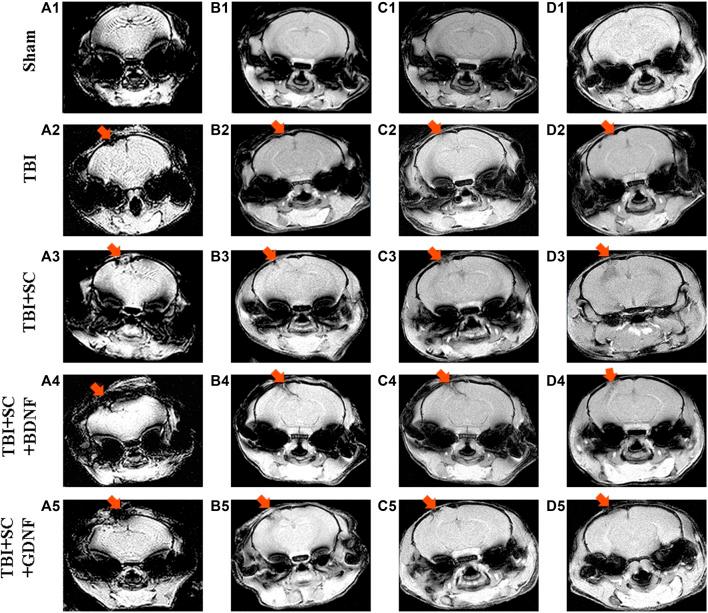

Brain tissue reconstruction posttraumatic injury remains a long-standing challenge in neurotransplantology, where a tissue-engineering construct (scaffold, SC) with specific biochemical properties is deemed the most essential building block. Such three-dimensional (3D) hydrogel scaffolds can be formed using brain-abundant endogenous hyaluronic acid modified with glycidyl methacrylate by employing our proprietary photopolymerisation technique. Herein, we produced 3D hyaluronic scaffolds impregnated with neurotrophic factors (BDNF, GDNF) possessing 600 kPa Young's moduli and 336% swelling ratios. Stringent testing of fabricated scaffolds using primary hippocampal cultures revealed lack of significant cytotoxicity: the number of viable cells in the SC+BDNF (91.67 ± 1.08%) and SC+GDNF (88.69 ± 1.2%) groups was comparable to the sham values ( > 0.05). Interestingly, BDNF-loaded scaffolds promoted the stimulation of neuronal process outgrowth during the first 3 days of cultures development (day 1: 23.34 ± 1.46 µm; day 3: 37.26 ± 1.98 µm, < 0.05, vs sham), whereas GDNF-loaded scaffolds increased the functional activity of neuron-glial networks of cultures at later stages of cultivation (day 14) manifested in a 1.3-fold decrease in the duration coupled with a 2.4-fold increase in the frequency of Ca oscillations ( < 0.05, vs sham). studies were carried out using C57BL/6 mice with induced traumatic brain injury, followed by surgery augmented with scaffold implantation. We found positive dynamics of the morphological changes in the treated nerve tissue in the post-traumatic period, where the GDNF-loaded scaffolds indicated more favorable regenerative potential. In comparison with controls, the physiological state of the treated mice was improved manifested by the absence of severe neurological deficit, significant changes in motor and orienting-exploratory activity, and preservation of the ability to learn and retain long-term memory. Our results suggest in favor of biocompatibility of GDNF-loaded scaffolds, which provide a platform for personalized brain implants stimulating effective morphological and functional recovery of nerve tissue after traumatic brain injury.

创伤后脑组织重建在神经移植学中仍然是一个长期存在的挑战,在该领域,具有特定生化特性的组织工程构建体(支架,SC)被认为是最基本的组成部分。通过使用我们专有的光聚合技术,可以利用甲基丙烯酸缩水甘油酯修饰的脑内丰富的内源性透明质酸形成这种三维(3D)水凝胶支架。在此,我们制备了负载神经营养因子(BDNF、GDNF)的3D透明质酸支架,其杨氏模量为600 kPa,溶胀率为336%。使用原代海马培养物对制备的支架进行严格测试,结果显示没有明显的细胞毒性:SC+BDNF组(91.67±1.08%)和SC+GDNF组(88.69±1.2%)的活细胞数量与假手术组相当(>0.05)。有趣的是,负载BDNF的支架在培养发育的前3天促进了神经元突起生长的刺激(第1天:23.34±1.46μm;第3天:37.26±1.98μm,与假手术组相比,<0.05),而负载GDNF的支架在培养后期(第14天)增加了培养物中神经元-胶质网络的功能活性,表现为持续时间减少1.3倍,同时钙振荡频率增加2.4倍(与假手术组相比,<0.05)。使用诱导创伤性脑损伤的C57BL/6小鼠进行研究,随后进行手术并植入支架。我们发现在创伤后时期,治疗的神经组织形态变化呈现积极动态,其中负载GDNF的支架显示出更有利的再生潜力。与对照组相比,治疗小鼠的生理状态得到改善,表现为没有严重的神经功能缺损、运动和定向探索活动没有显著变化,并且保留了学习和长期记忆的能力。我们的结果表明负载GDNF的支架具有生物相容性,为个性化脑植入物提供了一个平台,可刺激创伤性脑损伤后神经组织的有效形态和功能恢复。